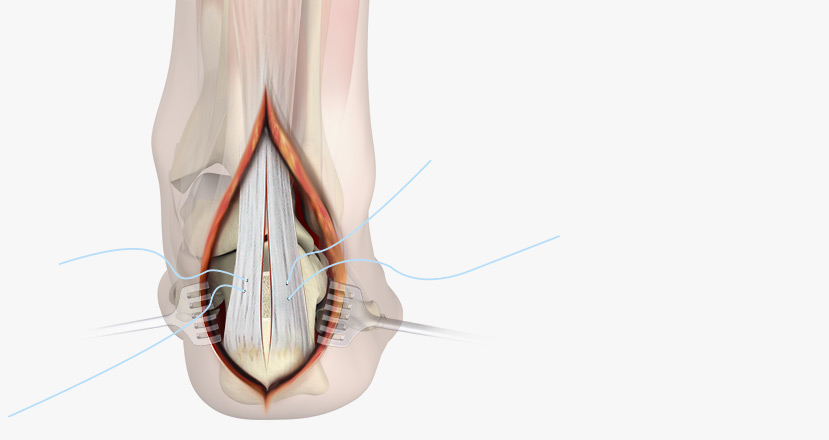

Exfix OP-techs